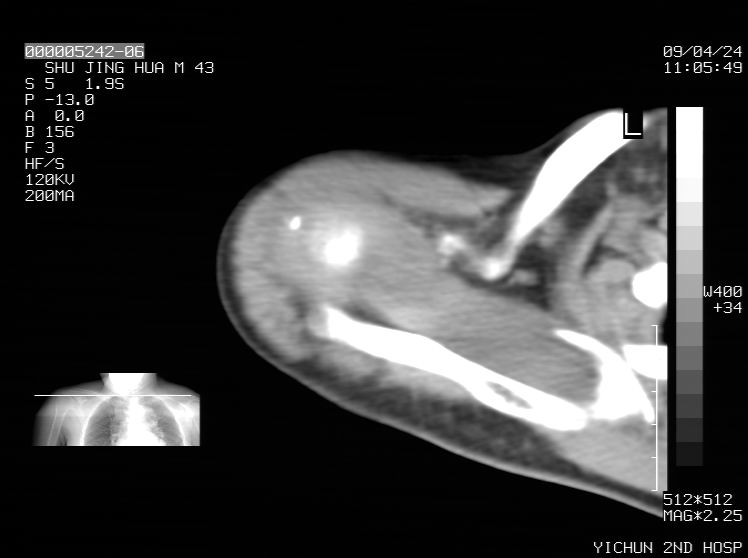

标题: CT19569:请会诊,女50岁,右肩疼痛数月 [打印本页]

标题: CT19569:请会诊,女50岁,右肩疼痛数月

钙化性肌腱炎

是指钙盐沉积在变性肌腱中的一种无菌性炎症,常见于肩关节的肩袖肌腱,引起肩部疼痛和活动受限。分为急性和慢性两种类型,急性型有肩关节突然出现急性疼痛的发作史,夜间可痛醒。

以下是引用余辉在2009-4-24 15:24:00的发言:[br]考虑钙化性肩周炎,肱二头肌长腱或相应附属组织钙化